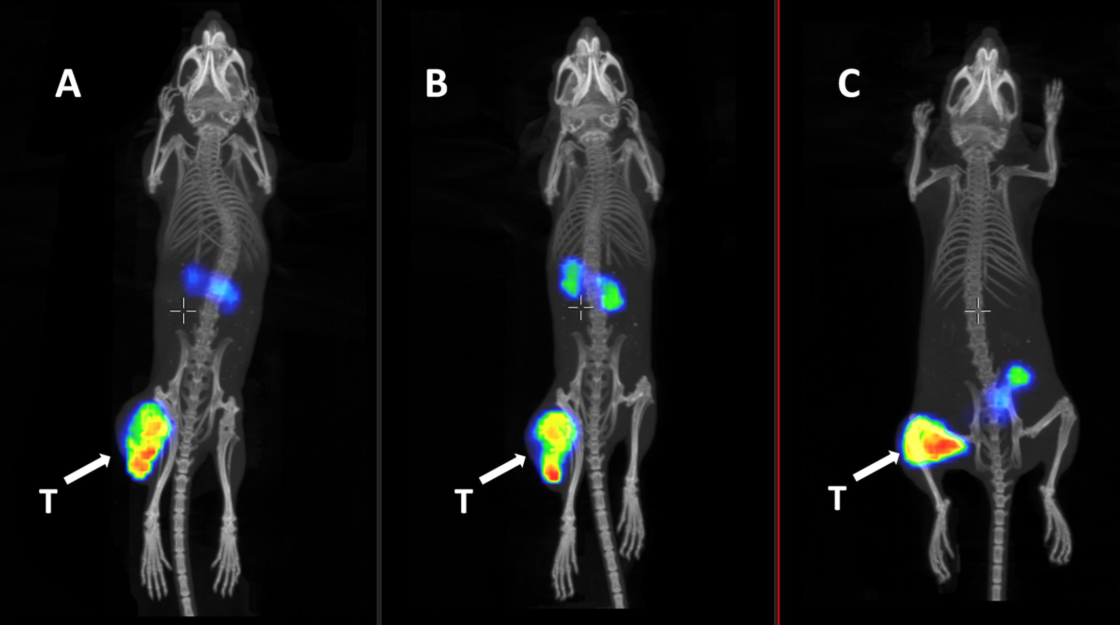

Figure 7. Representative nanoScan SPECT/CT images of PC3-pip xenografted mice injected with 5 nmol (1 MBq) [99mTc]Tc-BQ0413 (A), [99mTc]Tc-BQ0500 (B), and [99mTc]Tc-BQ0501 (C) at 3 h pi. The linear scale was adjusted to the first red pixel in the tumor. White arrows point to tumors (T).

Images acquired by the nanoScan® SPECT/CT indicated clear detection of the PSMA-expressing tumors and confirmed the results from ex vivo biodistribution.

The authors highlight that optimal clearance pattern permits detection of abdominal metastases, a reduction of activity in the gastrointestinal tract is crucial to further improve the imaging properties of [99mTc]Tc-BQ0501 as a promising probe for SPECT diagnostic imaging in PCa patients.